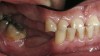

Figure 3  Intraoral occlusal view of mandibular dentition with the existing removable prosthesis presenting excessive signs of wear.

Figure 3

Initial examination revealed a partial edentulous patient with extensive wear of the maxillary anterior teeth and moderate wear in the mandibular teeth (Figure 1, Figure 2, Figure 3 , Figure 4, Figure 5, Figure 6 and Figure 7). The patient's maxillary and mandibular RPDs also showed excessive wear and multiple signs of fractures (Figure 2 and Figure 3). The patient had been wearing a mandibular nightguard for 8 years.